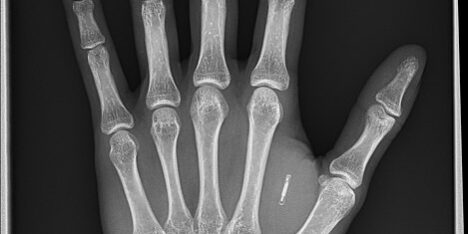

Takový čip umožní lidem létat bez pasu, otevírat dveře a nastartovat auta pouhým mávnutím rukou.

Americká společnost Dangerous Things již v roce 2017 prodala zákazníkům prostřednictvím svých webových stránek „desítky tisíc“ mikročipů. Podle zakladatelky Dangerous Things Amal Graafstra, která počítá, že se jednoho dne stanou stejně běžnými jako piercing nebo tetování, je nyní čas používat čipy více.